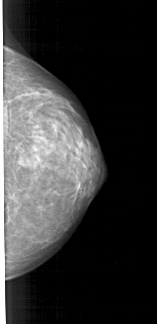

A_1379_1.RIGHT_MLO

RIGHT_MLO LINES 4966 PIXELS_PER_LINE 2086 BITS_PER_PIXEL 12 RESOLUTION 43.5 NON_OVERLAY